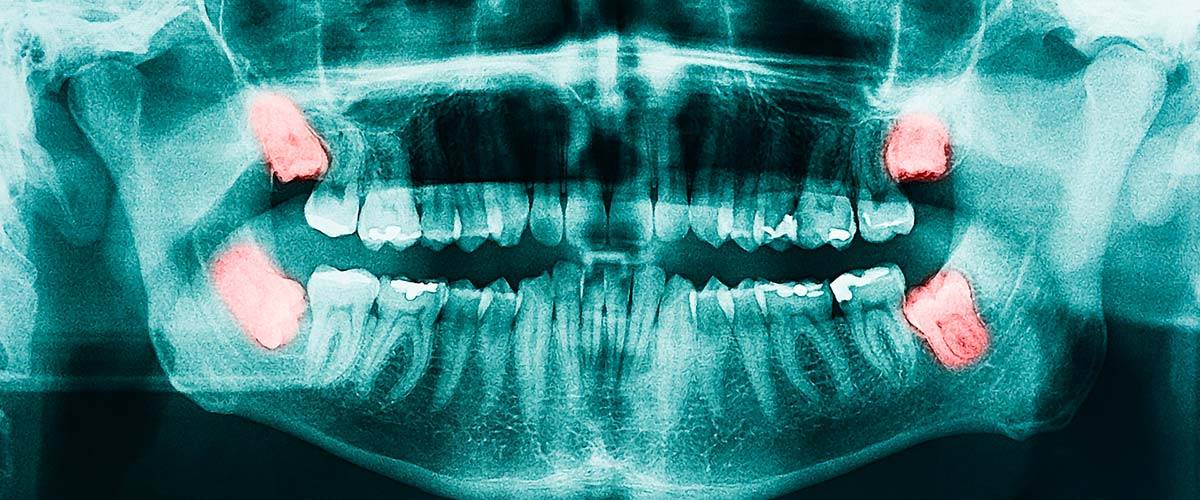

- Киста зуба — новообразование между зубным корнем и костью челюсти, имеет вид мешочка, заполненного гноем. Болезнь сопровождается ноющей болью, особенно сильно болит зуб при нажатии и воздействии на него горячей едой или напитками. Выявить кисту можно с помощью рентгенографии. Лечится она хирургическим путем. После удаления еще какое-то время может сохраняться боль, повышенная чувствительность и отечность десны.

- Ретинированный зуб мудрости. Непрорезавшиеся «восьмерки» часто начинают расти в сторону, нередко они давят на соседние зубы, вызывая болезненные ощущения. Также этот процесс сопровождается воспалением десны. Патологию легко диагностировать по локализации боли — за последним моляром, то есть на самом краю челюсти.